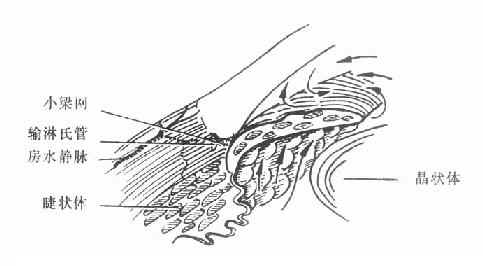

4.缓解期:急性发作的病例,大多数经过治疗,或者极少数未经治疗,症状消失,关闭的房角重新开放,眼压降至正常,病情可以得到暂时缓解,局部充血消失,角膜恢复透明,视力部分或完全恢复。个别短期无光感的病列,若及时降低眼压,尚可恢复一些有用视力。但这些情况只是暂时的,如不及时进行手术治疗,随时仍有急性发作的可能。此期称为急性闭角型青光眼缓解期,若及时施行周边虹膜节 除术,可防止急性发作。(图10-1,10-2)。

图10-2 闭角青光眼急性发作期(虹膜与小梁紧贴、房角关闭、无粘连)